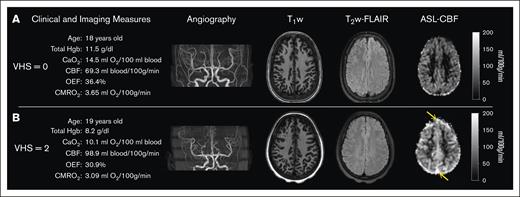

Table 2 summarizes the results from 2-way ANOVA analyses for main and interaction effects of VHS and age group (pediatric vs adult) on the clinical and imaging parameters; additionally, representative images and measures from 2 case examples are highlighted in Figure 3. Total Hb (F(2,137) = 9.334; P < .001) and CaO2 (Figure 4A; F(2,137) = 8.746; P < .001) were significantly different between VHS groups; specifically, both hematologic measures were reduced in participants with SCD with imaging evidence suggestive of rapid arteriovenous transit, defined as VHS = 2, compared with their counterparts with VHS = 0 (total Hb: Scheffe P = .001; CaO2: Scheffe P = .002) or VHS = 1 (total Hb: Scheffe P = .005; CaO2: Scheffe P = .009). Arterial oxygenation (F(1,137) = 7.692; P = .006) was significantly different between age groups; specifically arterial oxygenation was lower in adult participants than in pediatric participants (Scheffe P = .019). Eight participants (5.59%) did not have measured HbS percentages and were subsequently excluded from analysis with HbS percentage. Of the remaining participants, there was a significant interaction effect between VHS and age group on HbS percentage (F(2,129) = 3.472; P = .034).

Case examples. Demographic, clinical, and imaging measures are presented alongside angiography, T1-weighted, T2-FLAIR, and CBF images for 2 age-matched individuals with SCD and (A) VHS of 0 and (B) VHS of 2 on ASL MRI. The individual with VHS of 2 (B) had lower total Hb and arterial blood oxygen content; and displayed elevated CBF, reduced OEF, and reduced CMRO2 compared with the individual with VHS of 0 (A). Orange arrows on panel B indicate evidence of signal hyperintensity in the superior sagittal sinus on ASL MRI.